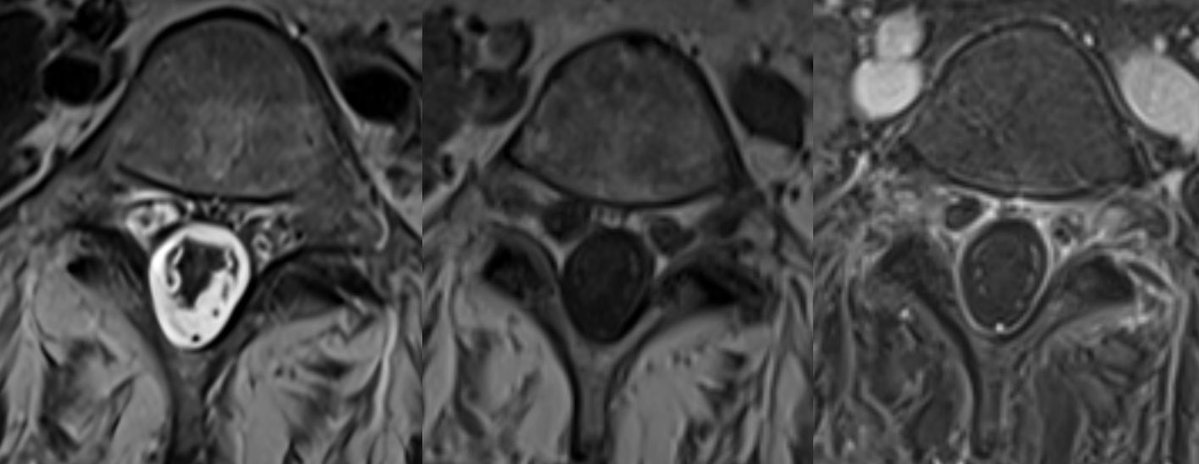

Important pitfalls: absence of obvious flow voids on MRI does not exclude the diagnosis. CSF is often abnormal (elevated RBCs protein common), but pleocytosis is uncommon.

Any unexplained thoracic myelopathy extending to the conus should prompt a thorough evaluation for a spinal dural AV fistula.